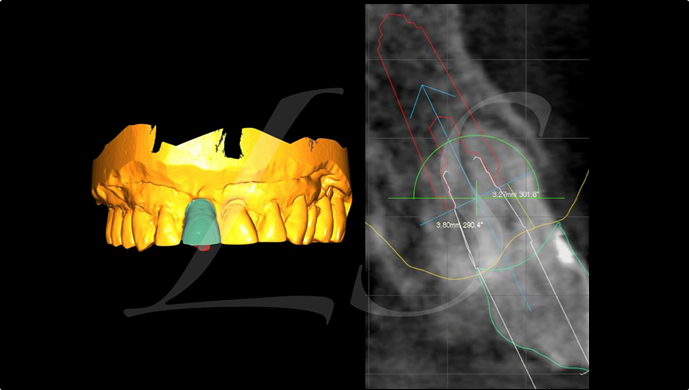

“Automated customized drilling protocols for optimum implant stability/ ONE-DAY implants ”

Clinical case: : Immediate loading of lower molars using R2Gate prefabricated 3D-printed provisional restoration

- Courtesy of Dr. Sam Omar, Egypt -

Dr.Sam Omar, immediate loading, digital guided surgery, digital ONE-DAY implant, maxillary anterior, #21, guided surgery, immediate loading, AnyRidge, R2GATE, Mega ISQ, MEG Torq, R2GATE Full Surgical Kit

implant system, R2GATE Guide, R2GATE surgical kit (AnyRidge), Mega ISQ